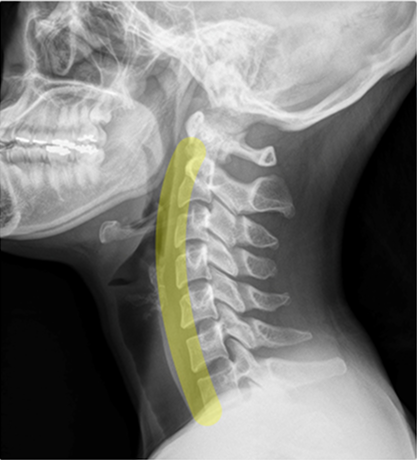

우리의 목은 C형태로 굽어 있습니다. 이를 '경추곡선'이라고 합니다. 무거운 머리를 수직 방향에서 안정적이고 효율적으로 받치기 위한 아치 구조입니다. 이 곡선이 자연스럽게 유지되는 것이 핵심입니다.

260129_brunch_img.png

(좌)목~엉덩이까지 이어지는 척추 곡선 / (우)경추 전만 곡선. C커브

① 뒤통수가 들리면서 경추가 C 커브에서 일(1) 자로 변합니다.

② 목이 들리면서 등에서 목으로 이어지는 근육이 과하게 늘어나 긴장합니다.

③ 그 결과 관절(디스크)과 근육에 모두 부담을 줍니다.